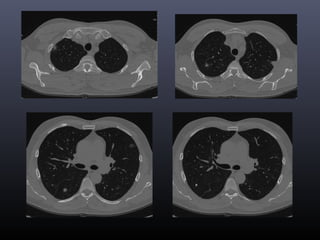

Tc torax 28-06-2011

• CONCLUSION TOMOGRAFICA:

• Nódulo pulmonar cavitado en el segmento 4 izquierdo con

afección de parénquima adyacente, lo cual como primera

posibilidad corresponde a Tuberculosis y diagnostico

diferencial de Coccidiodiomicosis.